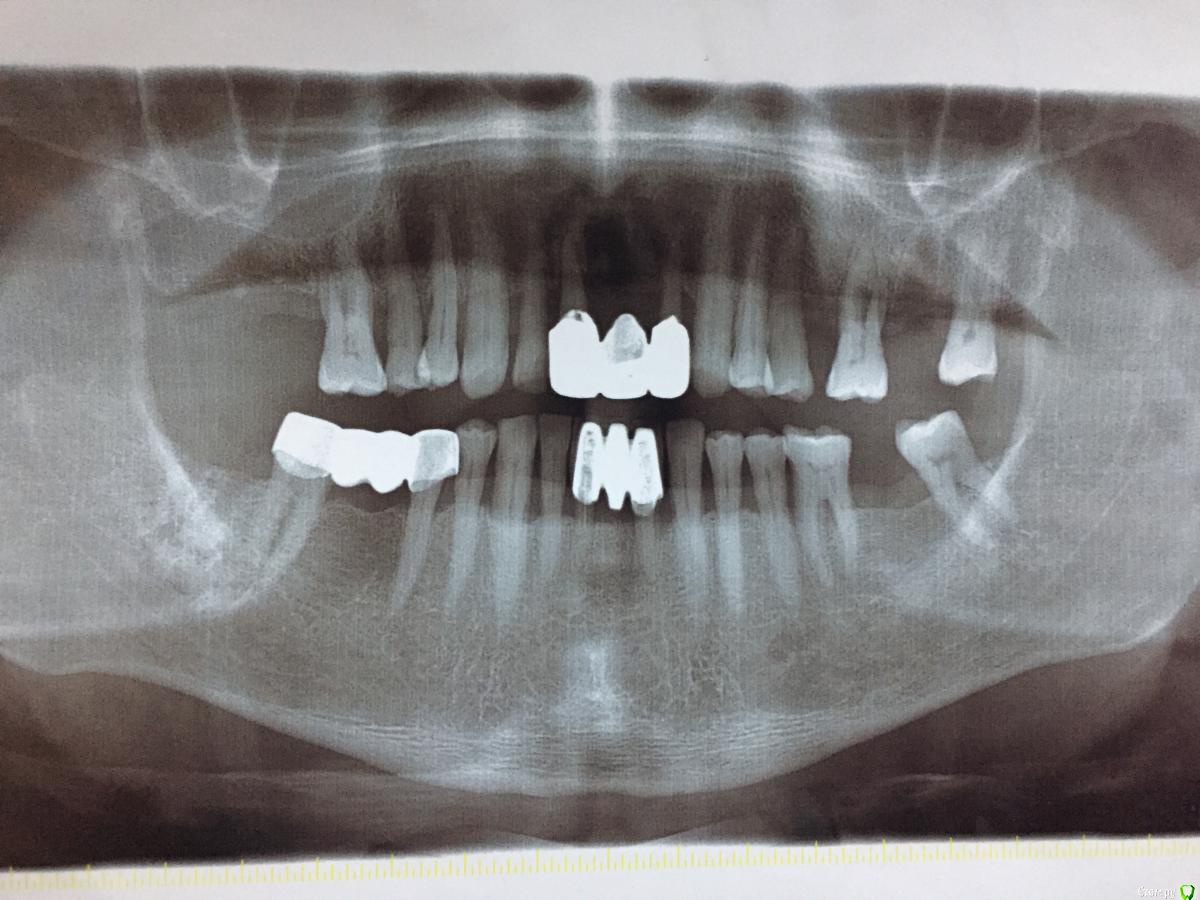

gum Опубликовано 3 января, 2017 Поделиться Опубликовано 3 января, 2017 Снимок покажите, может там и закрывать уже не надо. 1 Ссылка на комментарий

dok1 Опубликовано 3 января, 2017 Поделиться Опубликовано 3 января, 2017 Видно выдвижение. Возможно прощаться придётся. Ссылка на комментарий

ravshanmax Опубликовано 3 января, 2017 Автор Поделиться Опубликовано 3 января, 2017 25, 26 зубы шатаются 2 степени. С 28 до 24 мк будет. Потом 23-13 тоже мк. Но как быть когда корни до бифуркации видны. Как обточить, до десны закрыт или нет? Посоветуйте пожалуйста. Ссылка на комментарий

dok1 Опубликовано 4 января, 2017 Поделиться Опубликовано 4 января, 2017 Фуркация наруже - ничего хорошего. Ссылка на комментарий

gum Опубликовано 5 января, 2017 Поделиться Опубликовано 5 января, 2017 Лучше их не протезировать, особенно 6, но если собрались, то препарируйте до десны, чтоб не углубляться в область фуркации и не травмировать десну, если есть карман, то покюретажить было бы неплохо Ссылка на комментарий

PLAY Опубликовано 6 января, 2017 Поделиться Опубликовано 6 января, 2017 такие зубы нельзя пилить до десны, усугубите дефект фуркации и сильно спилите зуб, от него ничего почти не останется. Ссылка на комментарий

arsen147 Опубликовано 7 января, 2017 Поделиться Опубликовано 7 января, 2017 Удалите 26 и 11 и 22, курс лечения пародонта. шинировать оставшиеся подвижные зубы и съемник частичный .диспансеризация и т.д. Ссылка на комментарий